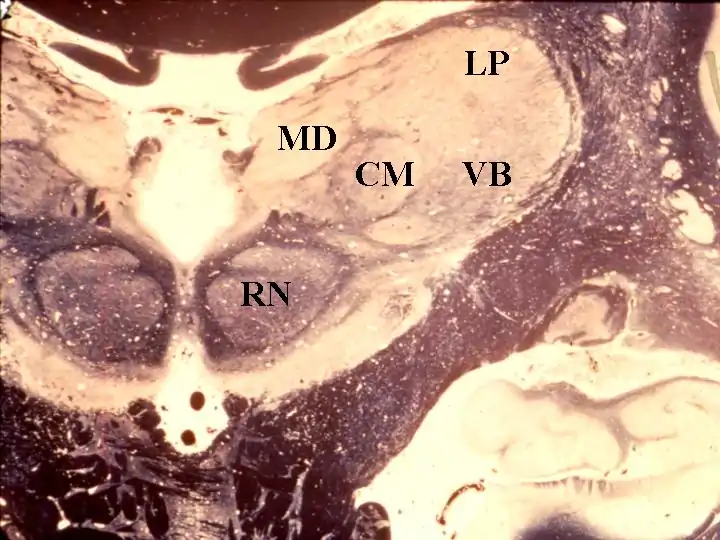

- The cortex and thalamus

- The Role of the Thalamus

- General Anaesthesia and the Thalamus